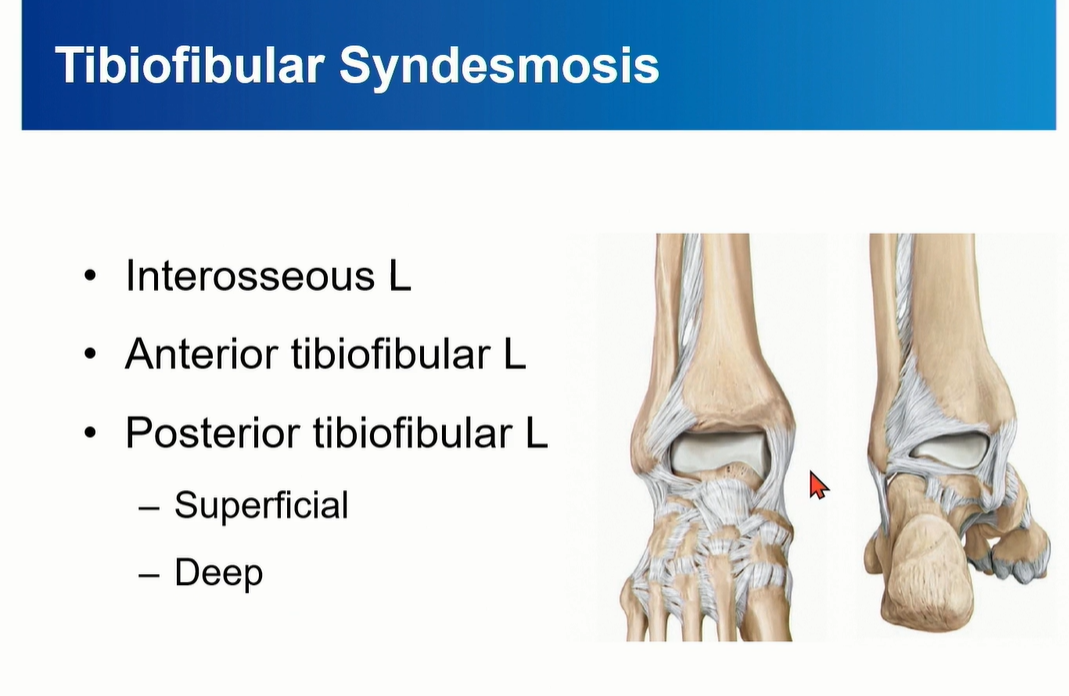

4. Distal tibiofibular syndemosis

Tibiofibular syndemosis = Interosseous Ligament + AITFL + PITFL

PITFL 은 superfical component와 deep component로 구성되는데, deep component를 inferior transverse ligament라고 부름.